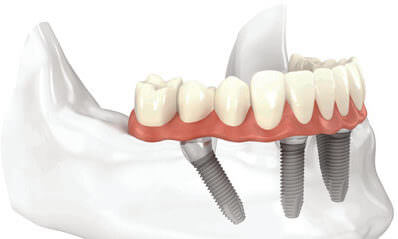

The All-On-4 treatment concept is a technique in which a fixed full arch prosthetic restoration is placed on 4-6 implants in the same day as the surgical operation. This treatment provides patient satisfaction by taking into account function, aesthetics, taste, speech, and self-confidence.

The All-on-4 treatment concept is a technique where a fixed full-arch prosthetic restoration is placed on 4-6 implants in a single day using the same titanium screw mechanism found in traditional implants. This treatment provides patient satisfaction by considering function, aesthetics, taste, speech, and confidence.

The main difference between traditional implants and All-on-4 implants is how they are positioned in the mouth. While 8 to 10 implants are required to replace missing teeth in a completely edentulous jaw using traditional implants, only 4 implants are needed with this new technique.

Two implants are placed in the thickest part of the bone in the front and two implants are placed in the back of the jawbone. The front implants are placed at a 90-degree angle, while the back implants are placed at a 45-degree angle to provide maximum stability. After the 4 implants are placed, bridges or crowns are attached to the implants.

For the All-on-4 treatment, temporary prosthetics are prepared based on measurements taken from the patient before treatment. If the patient has teeth that need to be extracted, they are removed while the implants are being placed under local anesthesia. The temporary prosthetics are then attached to the implants using the measurements taken. After 3 months, the patient's permanent prosthetics are attached.